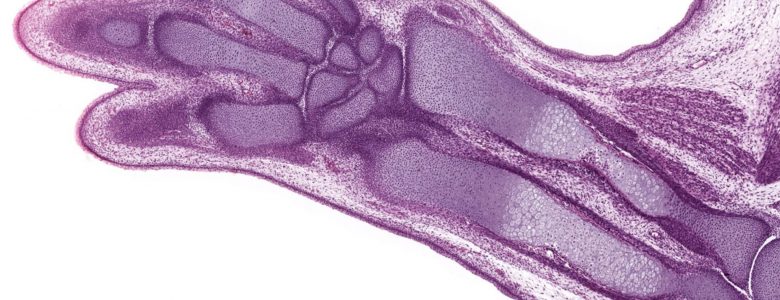

Endochondral ossification begins in a hyaline cartilage template of the future bone. Cartilage located in the center of the cartilage template undergoes a series of degenerative changes, forming a framework on which bone can be deposited. This bone is deposited on and replaces where cartilage has been located;  therefore, this deposition is termed endochondral ossification. Additionally, a sleeve of bone, the periosteal band, is deposited by intramembranous ossification around the central cartilage shaft by the original periochondrium-turned-periosteum. Animal limb 10x